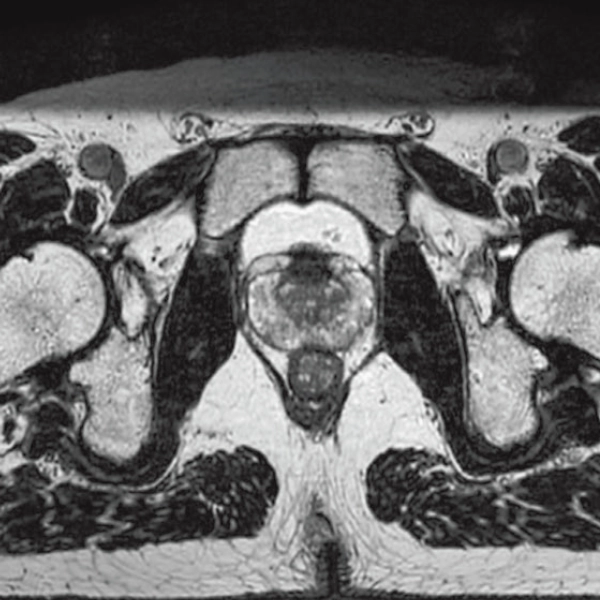

DLR offers 2 options

High Resolution

T2WI, 0.56×0.70×3.0mm, 2:28

T2*WI Multi Echo,

0.38×0.38×2.0mm

0.35×0.40×3.0mm, 2:55